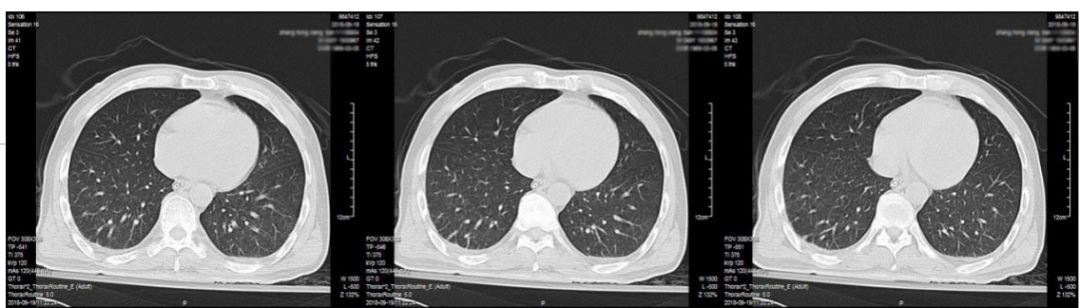

复查头部增强磁共振显示病灶较前有增大(图3)。胸部CT检查提示肺部感染合并少量胸腔积液(图4)

图4. 胸部CT,提示肺部感染合并少量胸腔积液。